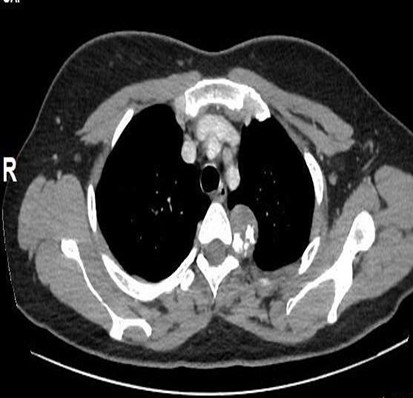

CECT scan was performed for better evaluation which showed a well defined lobulated hypodense mass lesion, lying in the left anterior paraspinal region at the level of the posterior end of the fourth rib. The lesion was arising from the posterior end of the left 4th rib. There were irregular nodular calcifications within it, and it measures ~3.1 (CC) x 2.6 (AP) x 2.5 (TR) cm. (Fig 2).

Figure 2. (A) CECT Thorax: Thin axial view showing a hypodense mass lesion arising from the posterior end of the 4th rib on the left side, irregular nodular seen calcifications within it. There is no obvious erosion of T4 vertebra. There is minimal enhancement in the mass lesion.

(B) Sagittal image showing the hypodense exophytic mass lesion in the posterior mediastinum.